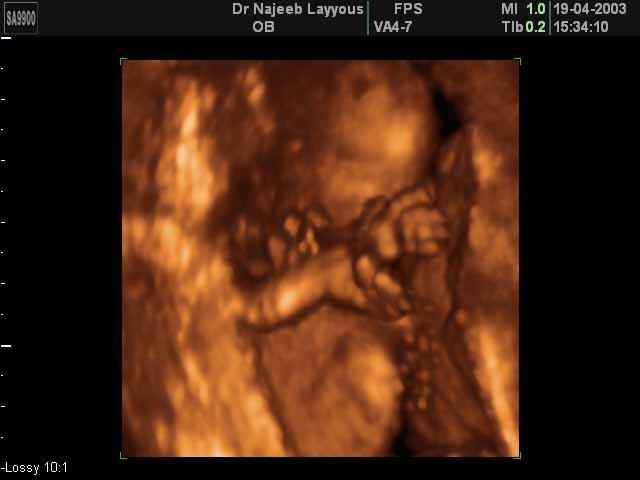

- 3D Fetal Limbs Ultrasound Scan Photos